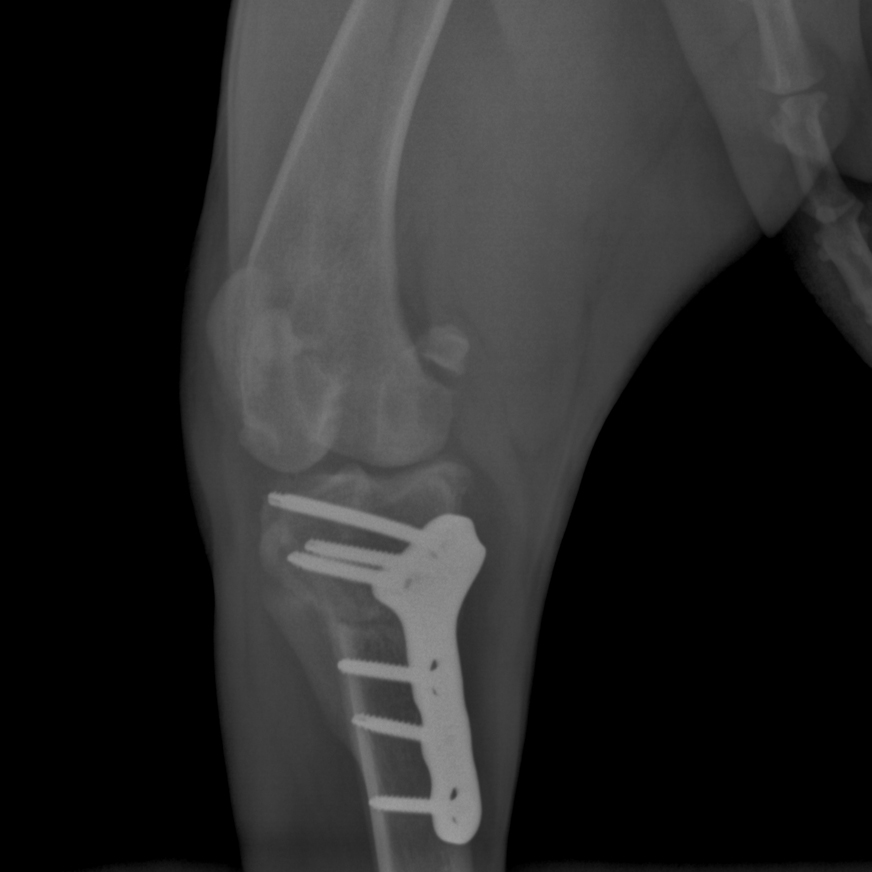

Tibial Plateau Leveling Osteotomy

This course is designed for veterinarians who want to specialize in orthopedic surgery and want to learn advanced techniques for managing knee injuries in small animals.